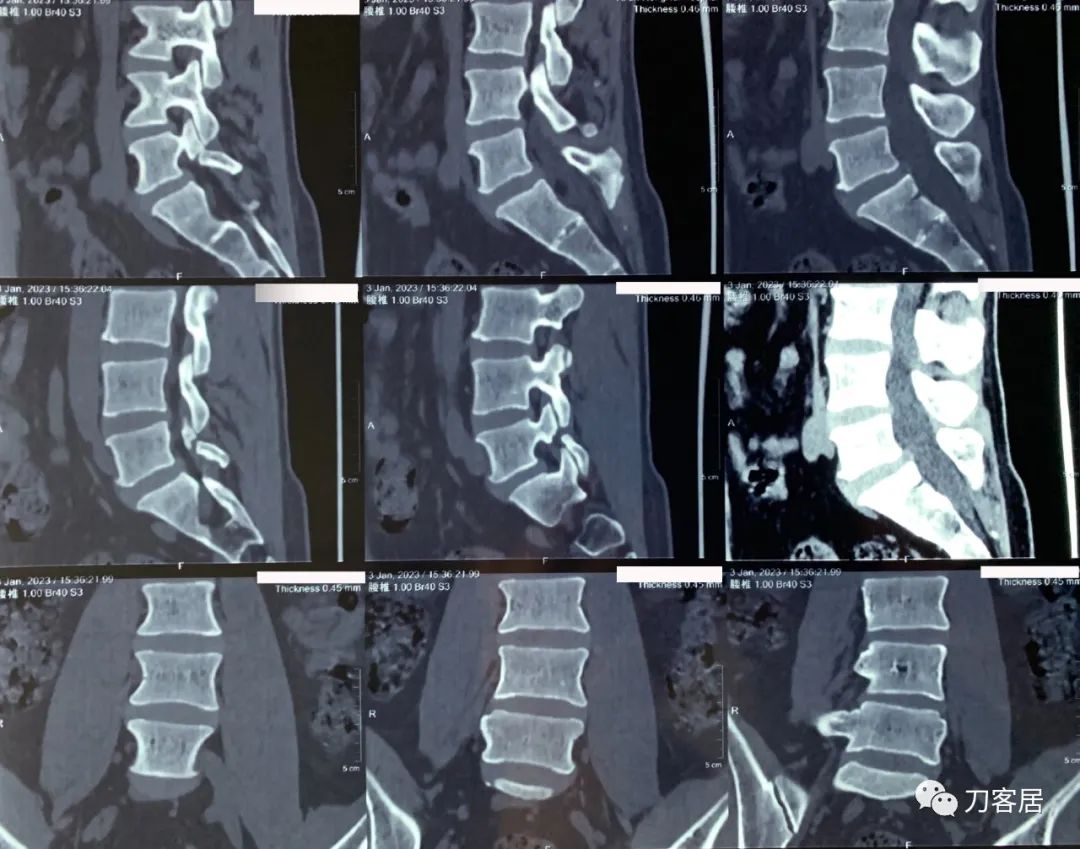

20230103西安某三甲医院腰椎CT

20230103西安某三甲医院腰椎CT报告。

腰椎CT片子提示腰5双侧峡部裂,无滑脱,无移位,有腰椎侧弯,但腰椎CT报告提示腰5有椎体滑脱1度。且有腰4-5、腰5骶1椎间盘突出,并未报告有腰椎侧弯。